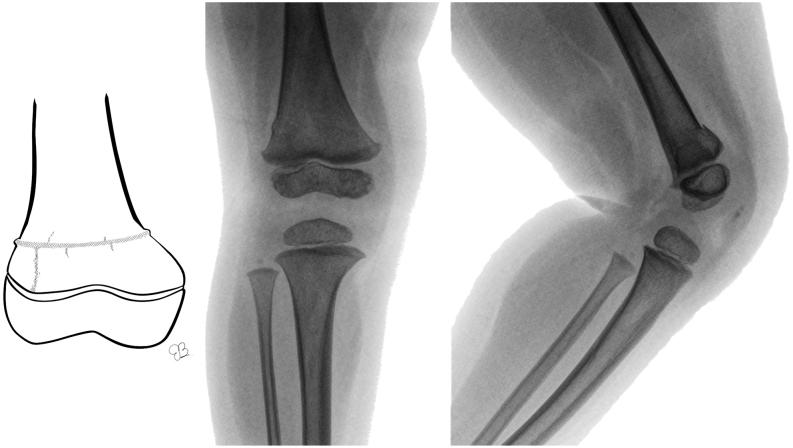

The physis of the distal femur contributes to 70% of femoral growth and 37% of the total limb growth; therefore, physeal injury can lead to important alterations of axes and length. Distal metaphyseal corner-type fracture prior to walking is classically associated with child abuse. In children aged >10 years, sports-related fractures and car accidents are significant contributors. Imaging includes a two-plane radiographic study of the knee. It is recommended to obtain radiographs that include the entire femur to rule out concomitant injuries. In cases of high suspicion of distal metaphyseal fractures and no radiographic evidence, CT or MRI can show the existence of hidden fractures. Fractures with physeal involvement are conventionally classified according to the Salter-Harris classification, but the Peterson classification is also recommended as it includes special subgroups. Conservative and surgical management are valid alternatives for the treatment of these fractures. Choosing between both alternatives depends on factors related to the fracture type. As there is a high risk of permanent physeal damage, long-term follow-up is essential until skeletal maturity is complete.

股骨远端的生长板对股骨生长的贡献率为70%,对整个肢体生长的贡献率为37%;因此,生长板损伤可导致轴线和长度的重要改变。行走前的远端干骺端角型骨折通常与虐待儿童有关。在10岁以上的儿童中,与运动相关的骨折和车祸是重要原因。影像学检查包括膝关节的双平面X线检查。建议获取包括整个股骨的X线片以排除合并损伤。在高度怀疑远端干骺端骨折但无X线证据的情况下,CT或MRI可显示隐匿性骨折的存在。涉及生长板的骨折传统上根据Salter-Harris分类法进行分类,但也推荐使用Peterson分类法,因为它包括特殊的亚组。保守治疗和手术治疗都是治疗这些骨折的有效选择。在这两种选择之间做出决定取决于与骨折类型相关的因素。由于存在永久性生长板损伤的高风险,因此在骨骼成熟完全之前进行长期随访至关重要。